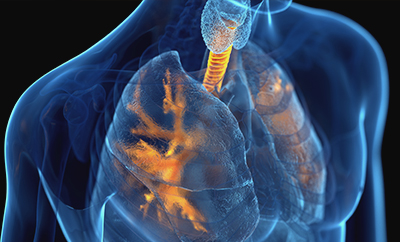

첨단 The Spirokit 기기로 호흡 데이터를 분석하여, 대학병원급 정밀도로 만성 폐질환(COPD)을 조기에 발견하는 AI 폐기능 검사를 시행합니다.